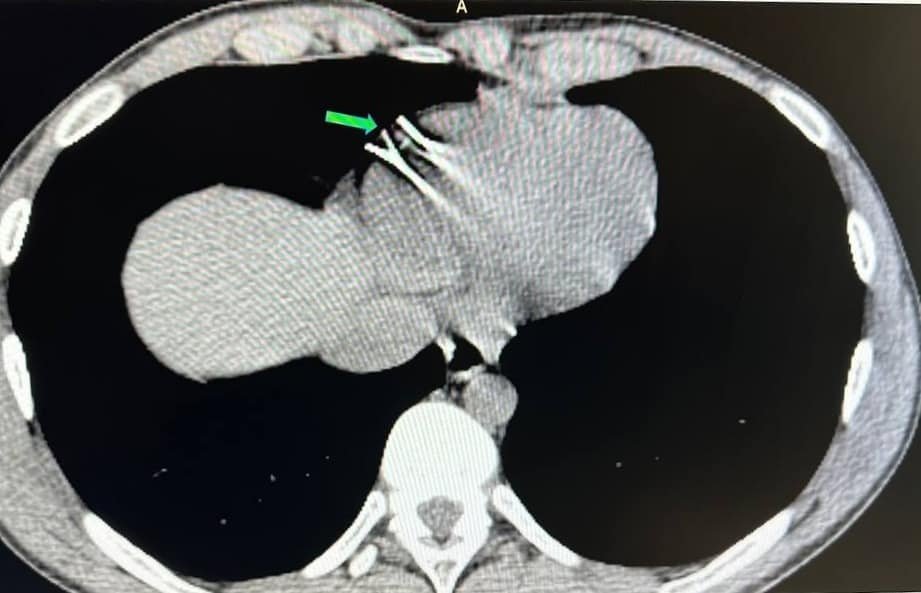

Вінницька обласна клінічна лікарня імені М. І. Пирогова повідомила, що 22-річний пацієнт зазнав проникаючої травми грудної клітини. Діагностичні процедури виявили два чужорідні тіла - металеві фрагменти у стінці правого шлуночка серця.

«7 березня, використовуючи гібридну операційну залу лікарні, було здійснено високотехнологічне хірургічне втручання без зупинки серця та кровообігу через мінімальний доступ - міні j-стернотомію. Операція включала використання передових методів рентгеннавігації та магнітних інструментів», - зазначається у звіті лікарні.